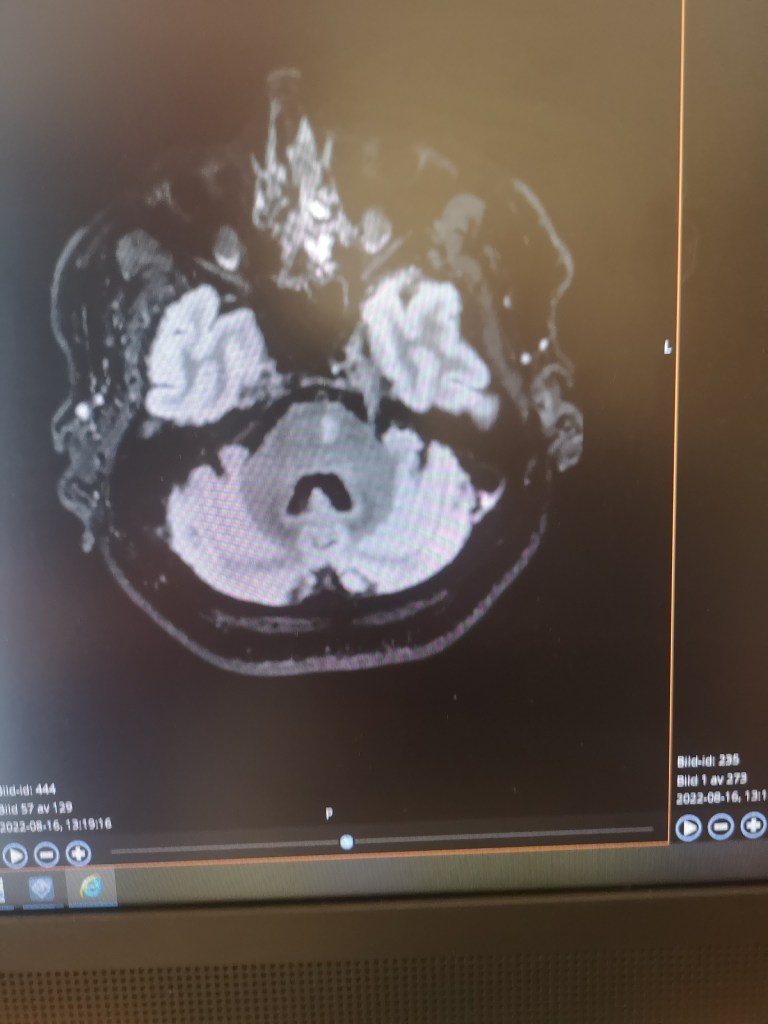

Han sade att jag skulle sluta med protonpumpshämmare (minskar magsyra och blödningsrisk) eftersom mitt immunförsvar sätts ned av det. Magsyran är väldigt viktig för mycket, inte minst för att slå ut olika patogener som man får i sig genom munnen. Risken för blödning i magen med 75 mg trombyl är minimal. Då är det bättre att ta protosonpumpshämmare först vid magkatarrskänsla, inte som förebyggande. Likaså skulle jag sluta med statiner då mina blodkärl var fina på MR. Så det var skönt att fortsättningsvis enbart behöva ta trombyl, som bara motsvarar 1/5 av en magnecyl.